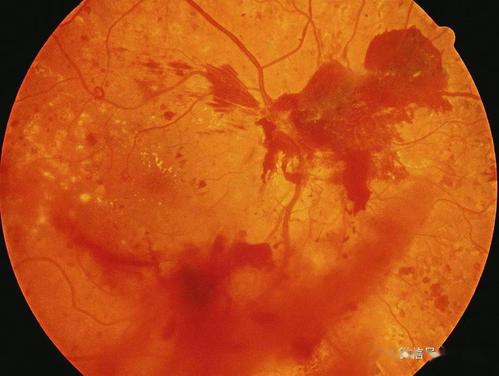

【功效主治】益气养阴固本,清热化瘀软坚。用于糖尿病视网膜病变。

【方解】糖尿病视网膜病变中医辨证有多种证型,但以气阴两虚最为常见,抓住主要证型,并随症加减用药可纲举目张。基本方以益气养阴固本为主,辅以清热化瘀软坚。黎老师尤喜用海螵峭与黄连,认为海螵峭是眼科软坚退翳要药,其性味咸涩微温,入肝、肾经,宜用于眼底渗出,虽有轻微伤阴助热之弊,但以黄连苦寒以平之,然黄连仅为佐药,不宜重用。

【加减】若情志抑郁比较明显,除做好心理引导外,可加疏肝安神药柴胡、白芍、郁金、五味子、首乌藤等;若有脾虚湿盛症状者,应去生地黄,西洋参改用党参,加苍术、蚕沙、藿香、白豆蔻等;兼见肝阳上亢者,可参考血压情况,选加石决明、首乌藤、夏枯草、决明子、葛根,并加服羚羊角胶囊;肥胖痰盛者,可参考血脂水平,去生地黄,西洋参改用党参,选加山楂、法半夏、茯苓、陈皮、天花粉、芜蔚子、何首乌;舌质暗红或兼见瘀点、少苔或无苔等有明显瘀血者,可参考血液流变学检查,加重丹参、桃仁用量;身体瘦弱,年龄较大的女性患者,有气血不足见证者,可加当归、白芍、何首乌。局部辨证:如早期仅见微血管瘤,应坚持方中丹参、桃仁的使用;痰浊渗出明显者,可加服珍珠末,每天3次,每次1支,酌加浙贝母、玄参,温燥祛痰药一般不宜选用;小出血点无需另加血分药,但应注意降虚火,滋肾阴。当血糖长期居高不降,或合并高血压及肾功能损害,眼底有可能突然大出血,往往是新生血管破裂所致,甚至血灌神膏,眼底镜不能透见眼内,应结合B超诊断,采取中西医措施紧急止血,处方中应加阿胶,并结合炭类止血药的使用。但治疗过程中,宜慎用破瘀化症药,如水蛭、虻虫、地龙、泽兰、三棱、莪术、川芎、穿山甲、蒲黄、虎杖、刘寄奴、牛膝之类,若使用不当,不但微血管瘤和渗出物不能祛除,反而有可能使新生血管破裂,酿成更大出血之患,应引起注意。故黎老师认为,治疗瘀血选药要讲究,药量不宜过重。若视网膜损害严重,痰瘀气血交结,应以整体辨治为宜。